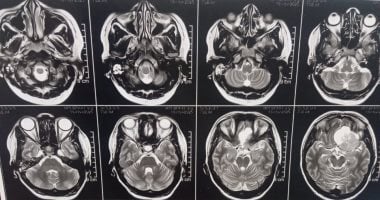

استئصال ورم ضخم بقاع الجمجمة لمريضة بمستشفى سوهاج الجامعى الأشعة التشخيصية للمريضة

وأوضح الدكتور مجدي القاضي، عميد كلية الطب البشري ورئيس مجلس إدارة المستشفيات الجامعية، أن المريضة كانت تعاني من صداع شديد وارتفاع ضغط المخ وتدهور في حدة الإبصار، وبإجراء الفحوصات الطبية وأشعة الرنين المغناطيسي، تبين وجود ورم كبير بقاع الجمجمة يضغط على أعصاب البصر والأوعية الدموية المغذية للمخ، ما استدعى التدخل الجراحي العاجل باستخدام أحدث التقنيات الدقيقة.